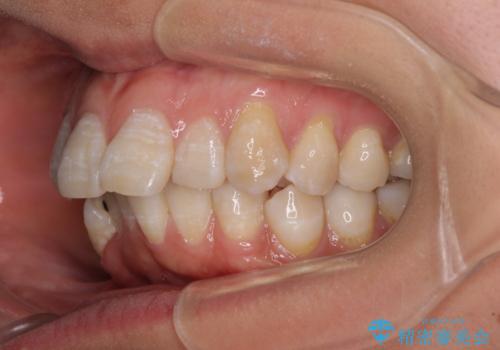

- 上顎歯列の出っ歯を気にして来院された患者様です。

骨格的に上顎歯列が前方位にあり、口元の突出感が顕著な状態で、上下左右の第一小臼歯4本を抜歯して、ワイヤー装置での抜歯矯正を行うこととしました。

ご本人がびっくりするくらい劇的に口元の突出感が改善され、大変満足のいく仕上がりとなりました。